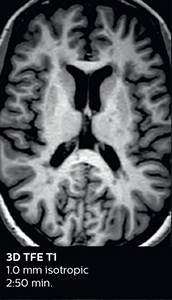

This is an example of acute ischemic stroke with distal occlusion of the right posterior cerebral artery. Note the improved visibility of the ischemic territory on the diffusion weighted image with high b-value. The 3D FLAIR shows a distal PCA occlusion. The fast SWIp depicts the thrombus on the isolated second echo image. The total scan time (including SmartBrain, preparations and a fast 3D T1w TSE Gd) is 8:00 minutes.